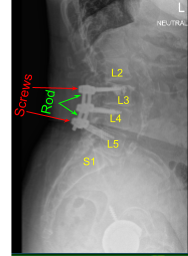

This patient had previously undergone an instrumented arthrodesis at an outside facility at L3-5. They presented with right anterior thigh and left posterior leg pain. Imaging displayed adjacent segment degeneration above and below her fusion mass which correlated well with her symptoms.